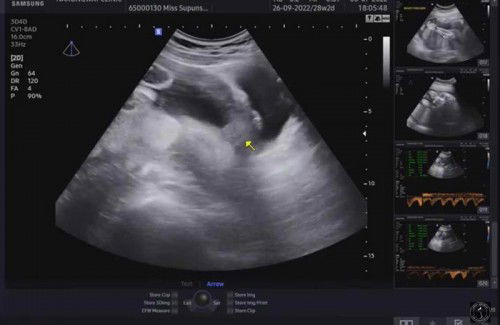

แบบนี้เพศอะไรคะ

แม่ๆช่วยดูเพศช่วยหน่อยค่ะ#ขอบคุณค่ะ#ท้องแรก#

รบกวนแม่ๆช่วยดูเพศช่วยหน่อยจ้า

ภาพลักษณะนี้ น้องคือเพศอะไรเหรอคะ คุณแม่ดูไม่ออกเลยค่ะ#ขอบคุณค่ะ🙏🏻

ไม่ค่อยชัดนะแม่